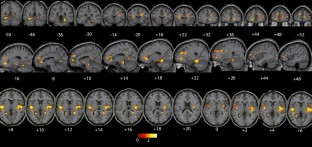

Idiomatic expressions (IE) are groups of words whose meaning is different from the sum of its components. Neural mechanisms underlying their processing are still debated, especially regarding lateralization, main structures involved, and whether this neural network is independent from the spoken language. To investigate the neural correlates of IE processing in healthy Spanish speakers.Twenty one native speakers of Spanish were asked to select one of 4 possible meanings for IE or literal sentences. fMRI scans were performed in a 3.0T scanner and processed by SPM 12 comparing IE vs. literal sentences. Laterality indices were calculated at the group level. IE activated a bilateral, slightly right-sided network comprising the pars triangularis and areas 9 and 10. In the left hemisphere (LH): the pars orbitalis, superior frontal, angular and fusiform gyrus. In the right hemisphere (RH): anterior insula, middle frontal, and superior temporal gyrus. This network reveals the importance of the RH, besides traditional LH areas, to comprehend IE. This agrees with the semantic coding model: the LH activates narrow semantic fields choosing one single meaning and ignoring others, and the RH detects distant semantic relationships, activating diffuse semantic fields. It is also in line with the configuration hypothesis: both meanings, literal and figurative, are executed simultaneously, until the literal meaning is definitively rejected and the figurative one is accepted. Processing IE requires the activation of fronto-temporal networks in both hemispheres. The results concur with previous studies in other languages, so these networks are independent from the spoken language. Understanding these mechanisms sheds light on IE processing difficulties in different clinical populations and must be considered when planning resective surgery.